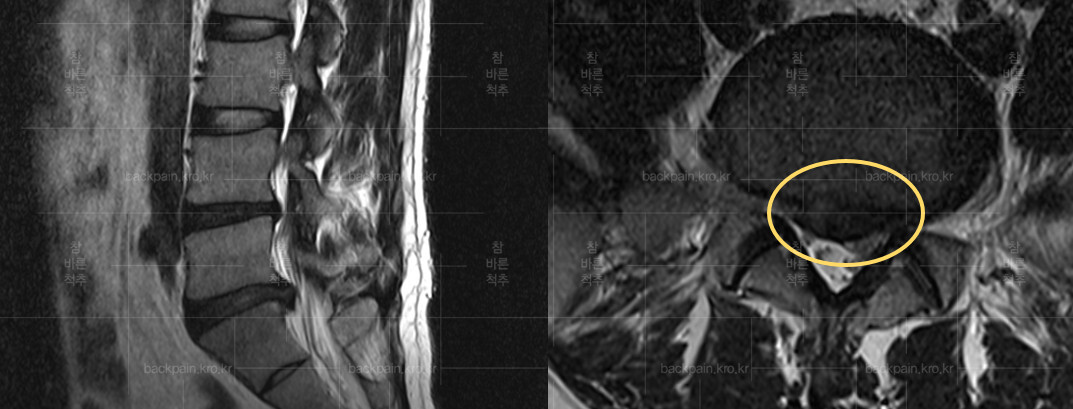

허리디스크는 척추의 구조를 이해하는 것이 중요합니다. 척추는 여러 개의 척추뼈로 이루어져 있으며, 이 사이에 디스크가 위치하고 있습니다. 디스크는 젤리같이 부풀어 있는 내부와 외부 섬유링으로 이루어져 있어 충격을 흡수하는 역할을 합니다. 그러나 여러 요인, 예를 들어 무리한 운동, 잘못된 자세, 노화 등으로 인해 디스크가 손상되거나 탈출하게 되면 심각한 통증을 유발할 수 있습니다.